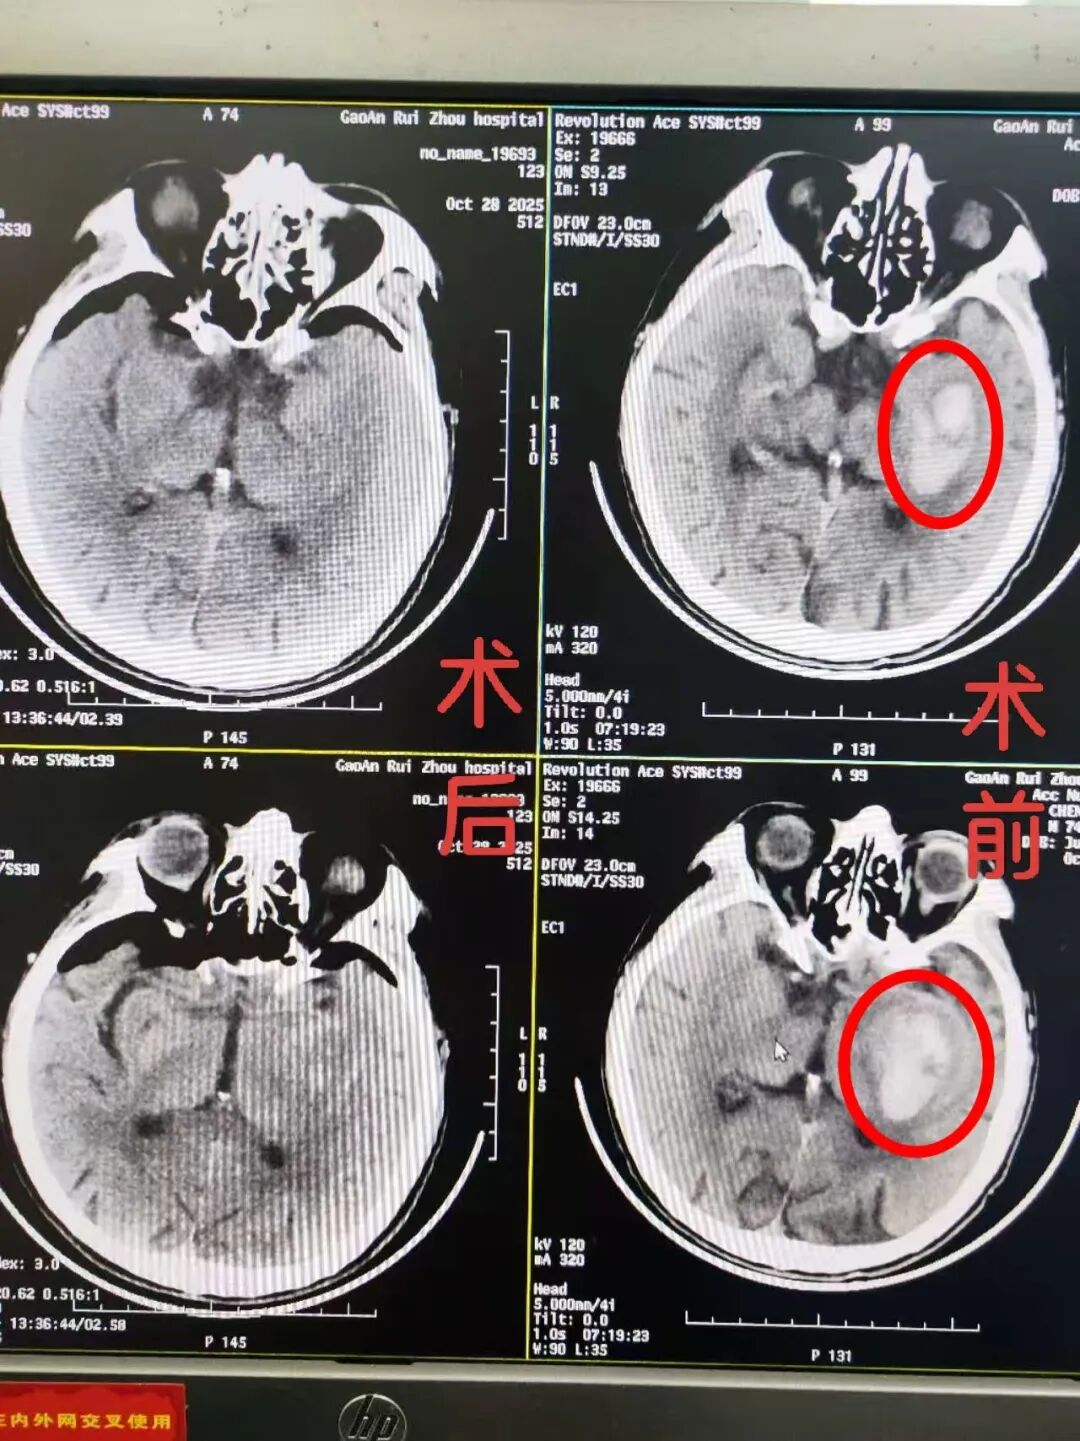

患者于2小时前无明显诱因突发意识不清(呼之能应,呈嗜睡状态),伴右侧肢体无力等症状。家属紧急送医后,急诊科立即启动卒中绿色通道,快速完成颅脑CT检查,结果明确显示“左侧基底节区脑出血”。病情危急,需立即住院治疗。

术中在颅内镜操作技术下,精准实施颅内血肿清除术,整个过程有条不紊、顺利完成。术后患者生命体征平稳,安返ICU严密监护。